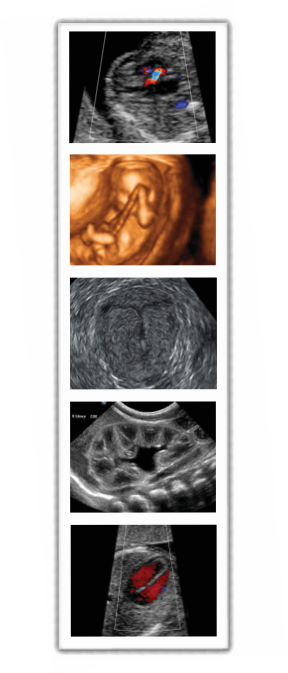

GENERAL & VASCULAR

ULTRASOUND

• Abdomen /Renal / Bladder

• Soft Tissue/ Thyroid / Testes / Eyes

• Carotids

• Aorta

• DVT

• Venous incompetence

• Arterial studies